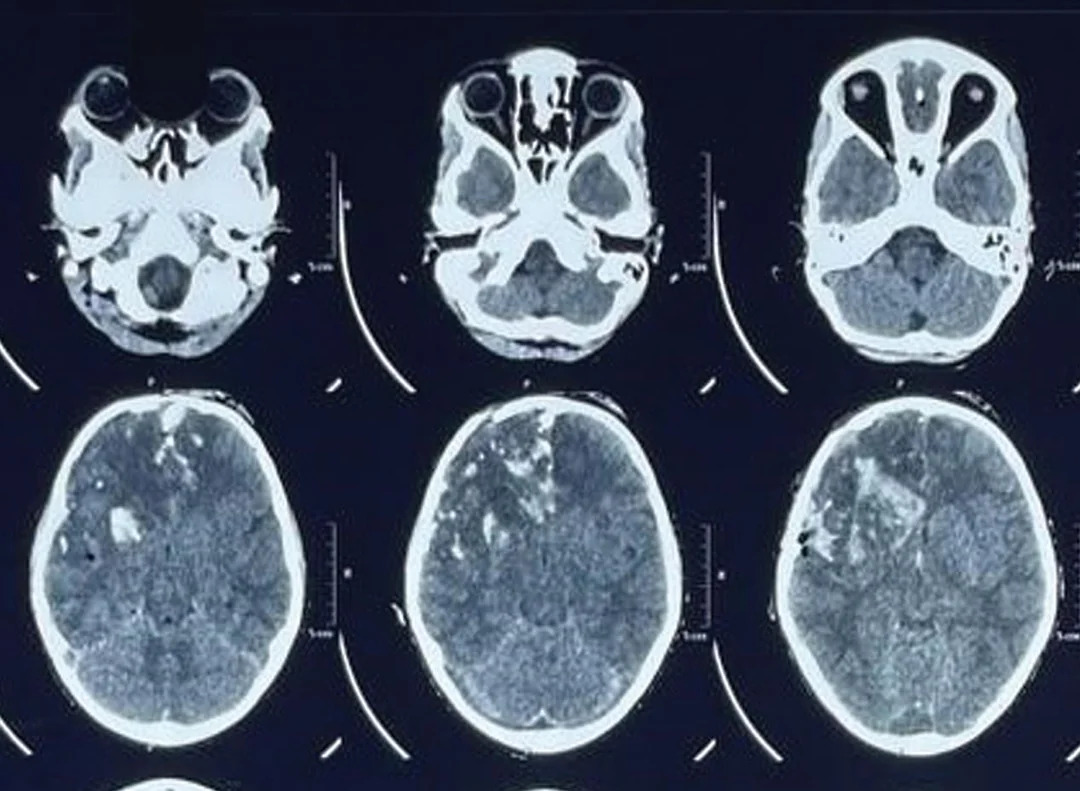

Fig 2: Resolving edema on postoperative day 8

Postoperatively patient was shifted to neuro intensive care unit and was kept on sedation and mechanical ventilation. He was started on cerebral decongestants, broad-spectrum antibiotic, and antiepileptic. On postoperative day 1, GCS was E1VTM5 status. A repeat NCCT head showed development of gross edema in the brain. Cerebral decongestants were continued and barbiturate coma was induced for next 48 hours. Tracheostomy was done on postoperative day 4. A repeat NCCT head on postoperative day 8 showed resolution of edema. His GCS also improved to E3VTM6 status (►Fig. 2). On postoperative day 14, he became E4VTM6. He was later shifted toward where he was decannulated. He developed left-sided hemiparesis for which he was started on physiotherapy. He underwent a prolonged neurorehabilitation and made a complete recovery after 3 months of injury (►Fig. 5).